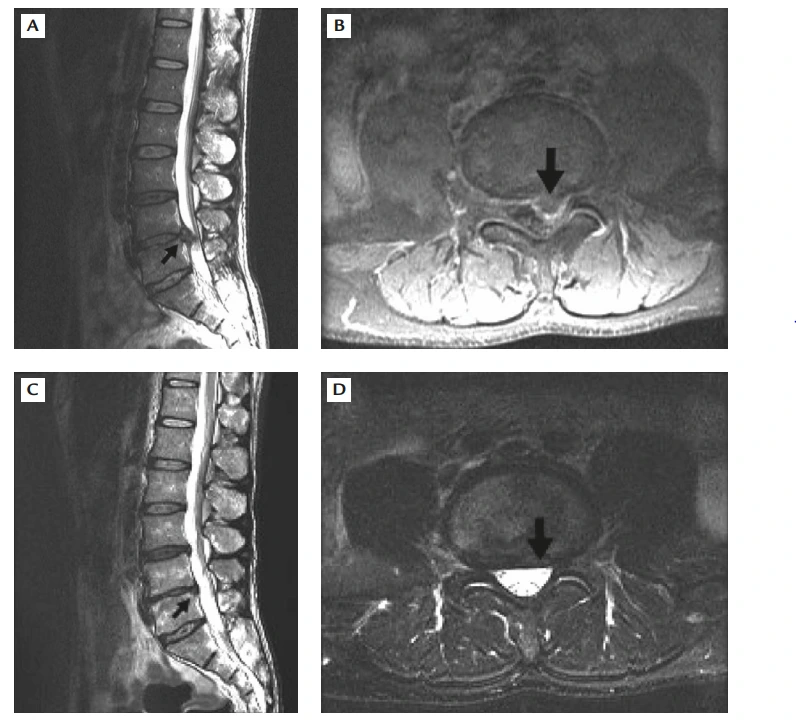

다른 환자를 보자.

A&B 사진의 표시된 곳을 보면, 요추 5번 - 천추 1번 사이의 디스크가 왼쪽을 심하게 누르고 있다. 환자는 심한 요통과 좌측 다리 방사통, 그리고 간헐적 파행(Claudication)을 보였다. 하지만 역시 마비 등 신경 증상은 없었기 때문에 보존적 치료(약물 치료, 휴식)를 시행하였다.

14개월 후의 사진 C&D 를 보면 이전 튀어나왔던 디스크 대부분이 흡수되어 사라졌음을 볼 수 있다.